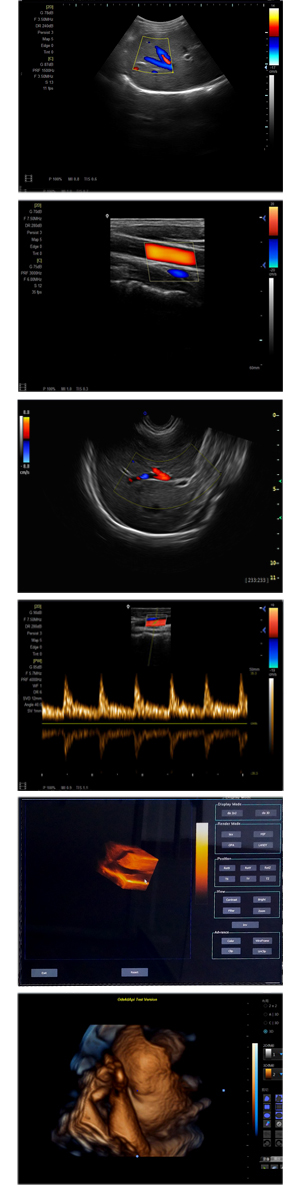

XF-7500型,秉承先鋒彩超技術之精華,擁有高雅大氣的獨特外型,為最新一代應用型數(shù)字彩色多普勒診斷系統(tǒng),魅力與實力相融合??蓮V泛適用于腹部、婦產(chǎn)科、心臟、小器官、乳腺、肌骨及外周血管等諸多方面的診查,讓您在臨床超聲診斷應用領域得心應手,綻放異彩!

● 3D/ 4D成像技術/選配

● 應用于腹部、腎臟、泌尿系統(tǒng)、產(chǎn)科、婦科、盆腔、大動脈、肌肉組織、小器官、乳腺、心臟等

● 能量多普勒成像(PDI)

● 彩色血流量圖(CDE)

● 脈沖頻譜多普勒成像(PW)